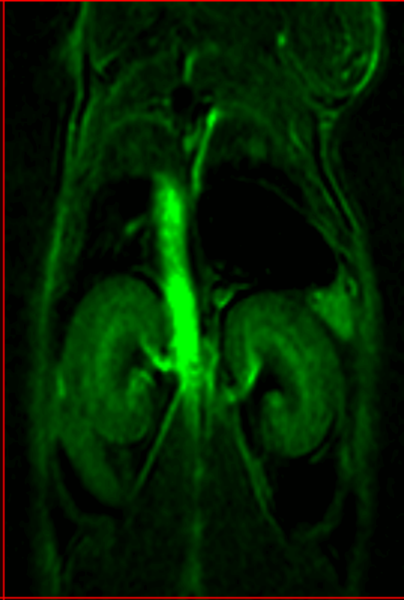

MR angiography with high T1 relaxivity liposomal-Gd contrast agents produces reconstructed 3D map of the cerebral vasculature of a mouse brain. Image Credit: Scintica Instrumentation Inc